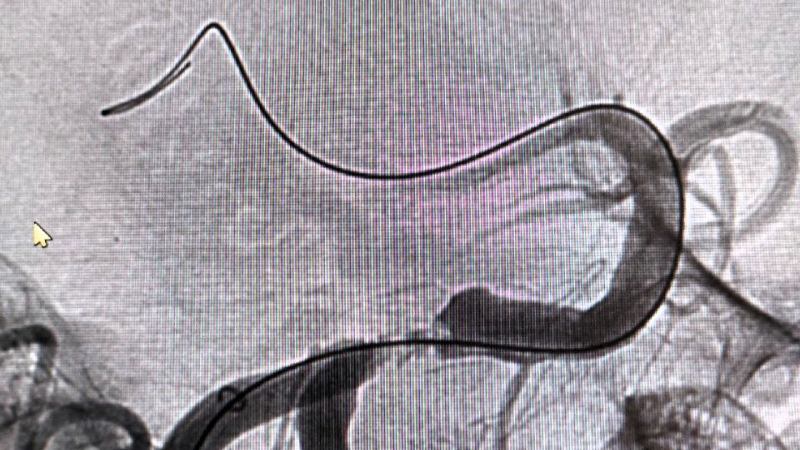

По словам заведующего отделением рентгенохирургических методов диагностики и лечения РСЦ Антона Аналеева, причиной стало образование атеросклеротической бляшки, перекрывшей главную артерию, снабжающую кровью ключевые участки мозга.

Благодаря вовремя поставленному диагнозу пациенту экстренно провели операцию, в ходе которой удалили тромб, а также установили стент.